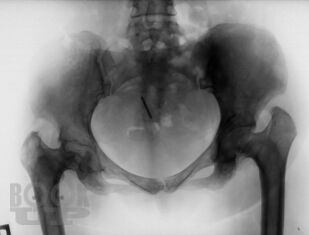

Болезнь Гоше относится к системным заболеваниям неопухолевой природы, в основе которых лежат наследственные дефекты метаболизма, приводящие к накоплению в органах и тканях нерасщепленных продуктов нормального обмена веществ. В случае болезни Гоше дефектом метаболизма является дефицит фермента, ответственного за метаболизм липидов.

Цель книги — познакомить врачей различных специальностей с основными клиническими проявлениями болезни Гоше, продемонстрировать исключительную вариабельность течения болезни на примере конкретных клинических случаев, показать характерные ошибки диагностики и ведения пациентов с болезнью Гоше. Помимо врачей, книга может быть полезной для образования самих пациентов и их родственников, так как некоторые особенности клинического течения заболевания напрямую связаны с социально-бытовыми аспектами: образом жизни, физической активностью, наличием бытовых интоксикаций и др.